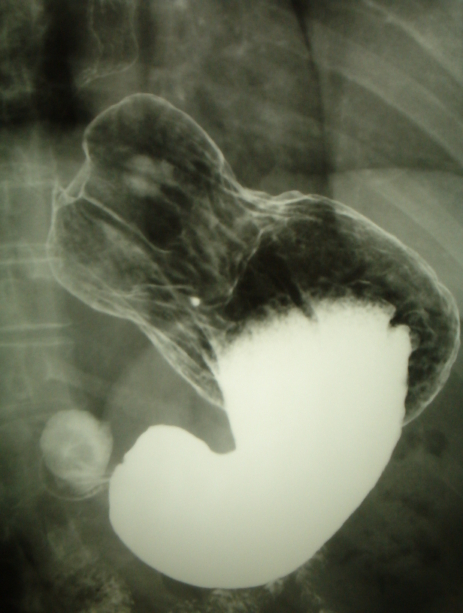

- Estudio radiológico con contraste (Tránsito esófago-gástrico). Consistente en tomar por boca contraste radio-opaco (papilla de bario) y hacer unas radiografías. Ayuda a definir la anatomía y nos demostrará la existencia de una hernia de hiato.